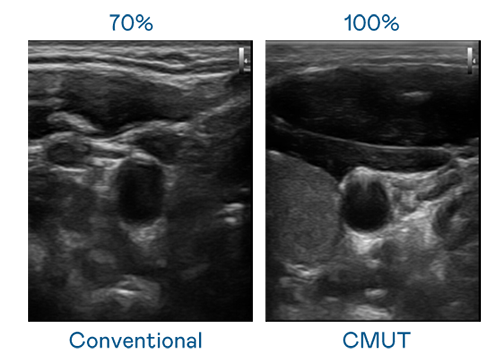

CMUT 技术是一种用电容式微机电元件来产生超音波讯号的技术。与传统 PZT 压电式技术相比,CMUT 频宽增加 30%,更宽频的超音波讯号让影像解析度大幅提升,是实现高影像品质医疗超音波扫描、促进精准医疗发展的关键技术。

大频宽带来超清晰影像

超音波影像的解析度高低,首先取决于探头能发出的讯号频宽。Maxman | 万博 CMUT 可提供高清晰的超音波讯号,提供高频宽、高灵敏度、影像纹理细节更高的超音波影像,协助医护人员缩短影像判读时间及利用精准的医疗影像进行诊断。